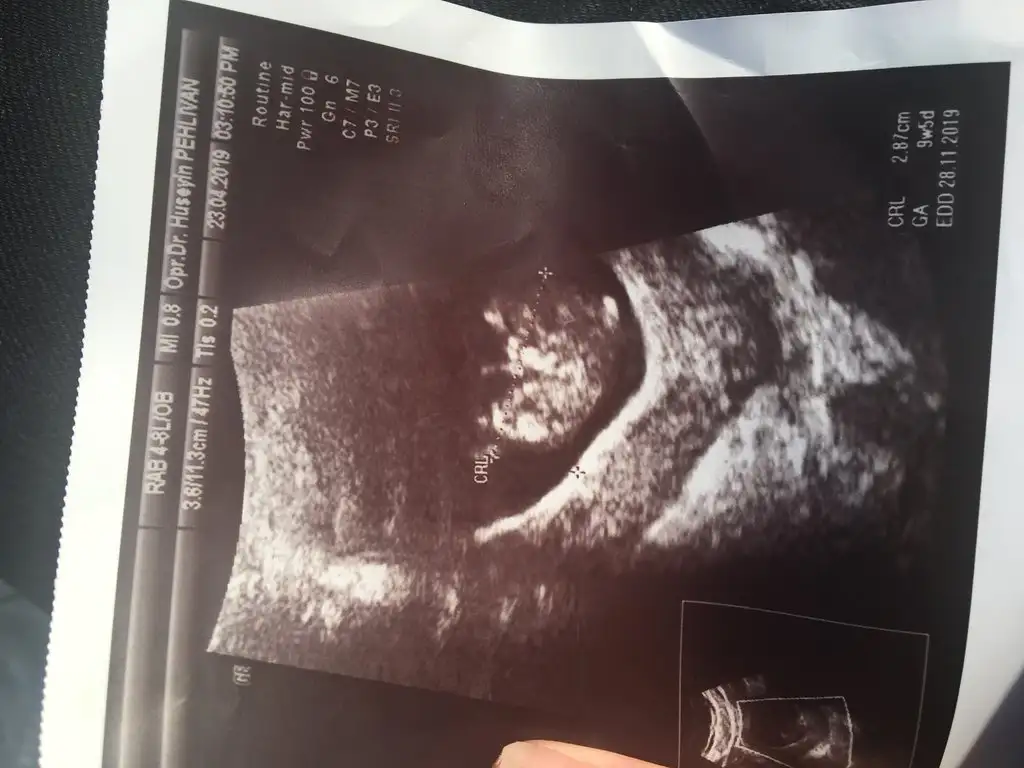

Kızlllar büzde 9+5 olmuşuzilk defa kalbıni duyduk kalp atımı 165 çok iyi dedi sadece suyu bol iç dedi su az dedi doğru söyledi su içmem durdu resmen midem bulanıyor resmen sizler nasıl yapıyorsunuz su içmek için lımonlu içsem acaba zararlı olurmu bilemedim bide resmini atsam tahmin yürütürmüsünüz kızlar cok merak ediyorumm Eki Görüntüle 2261725 Eki Görüntüle 2261725